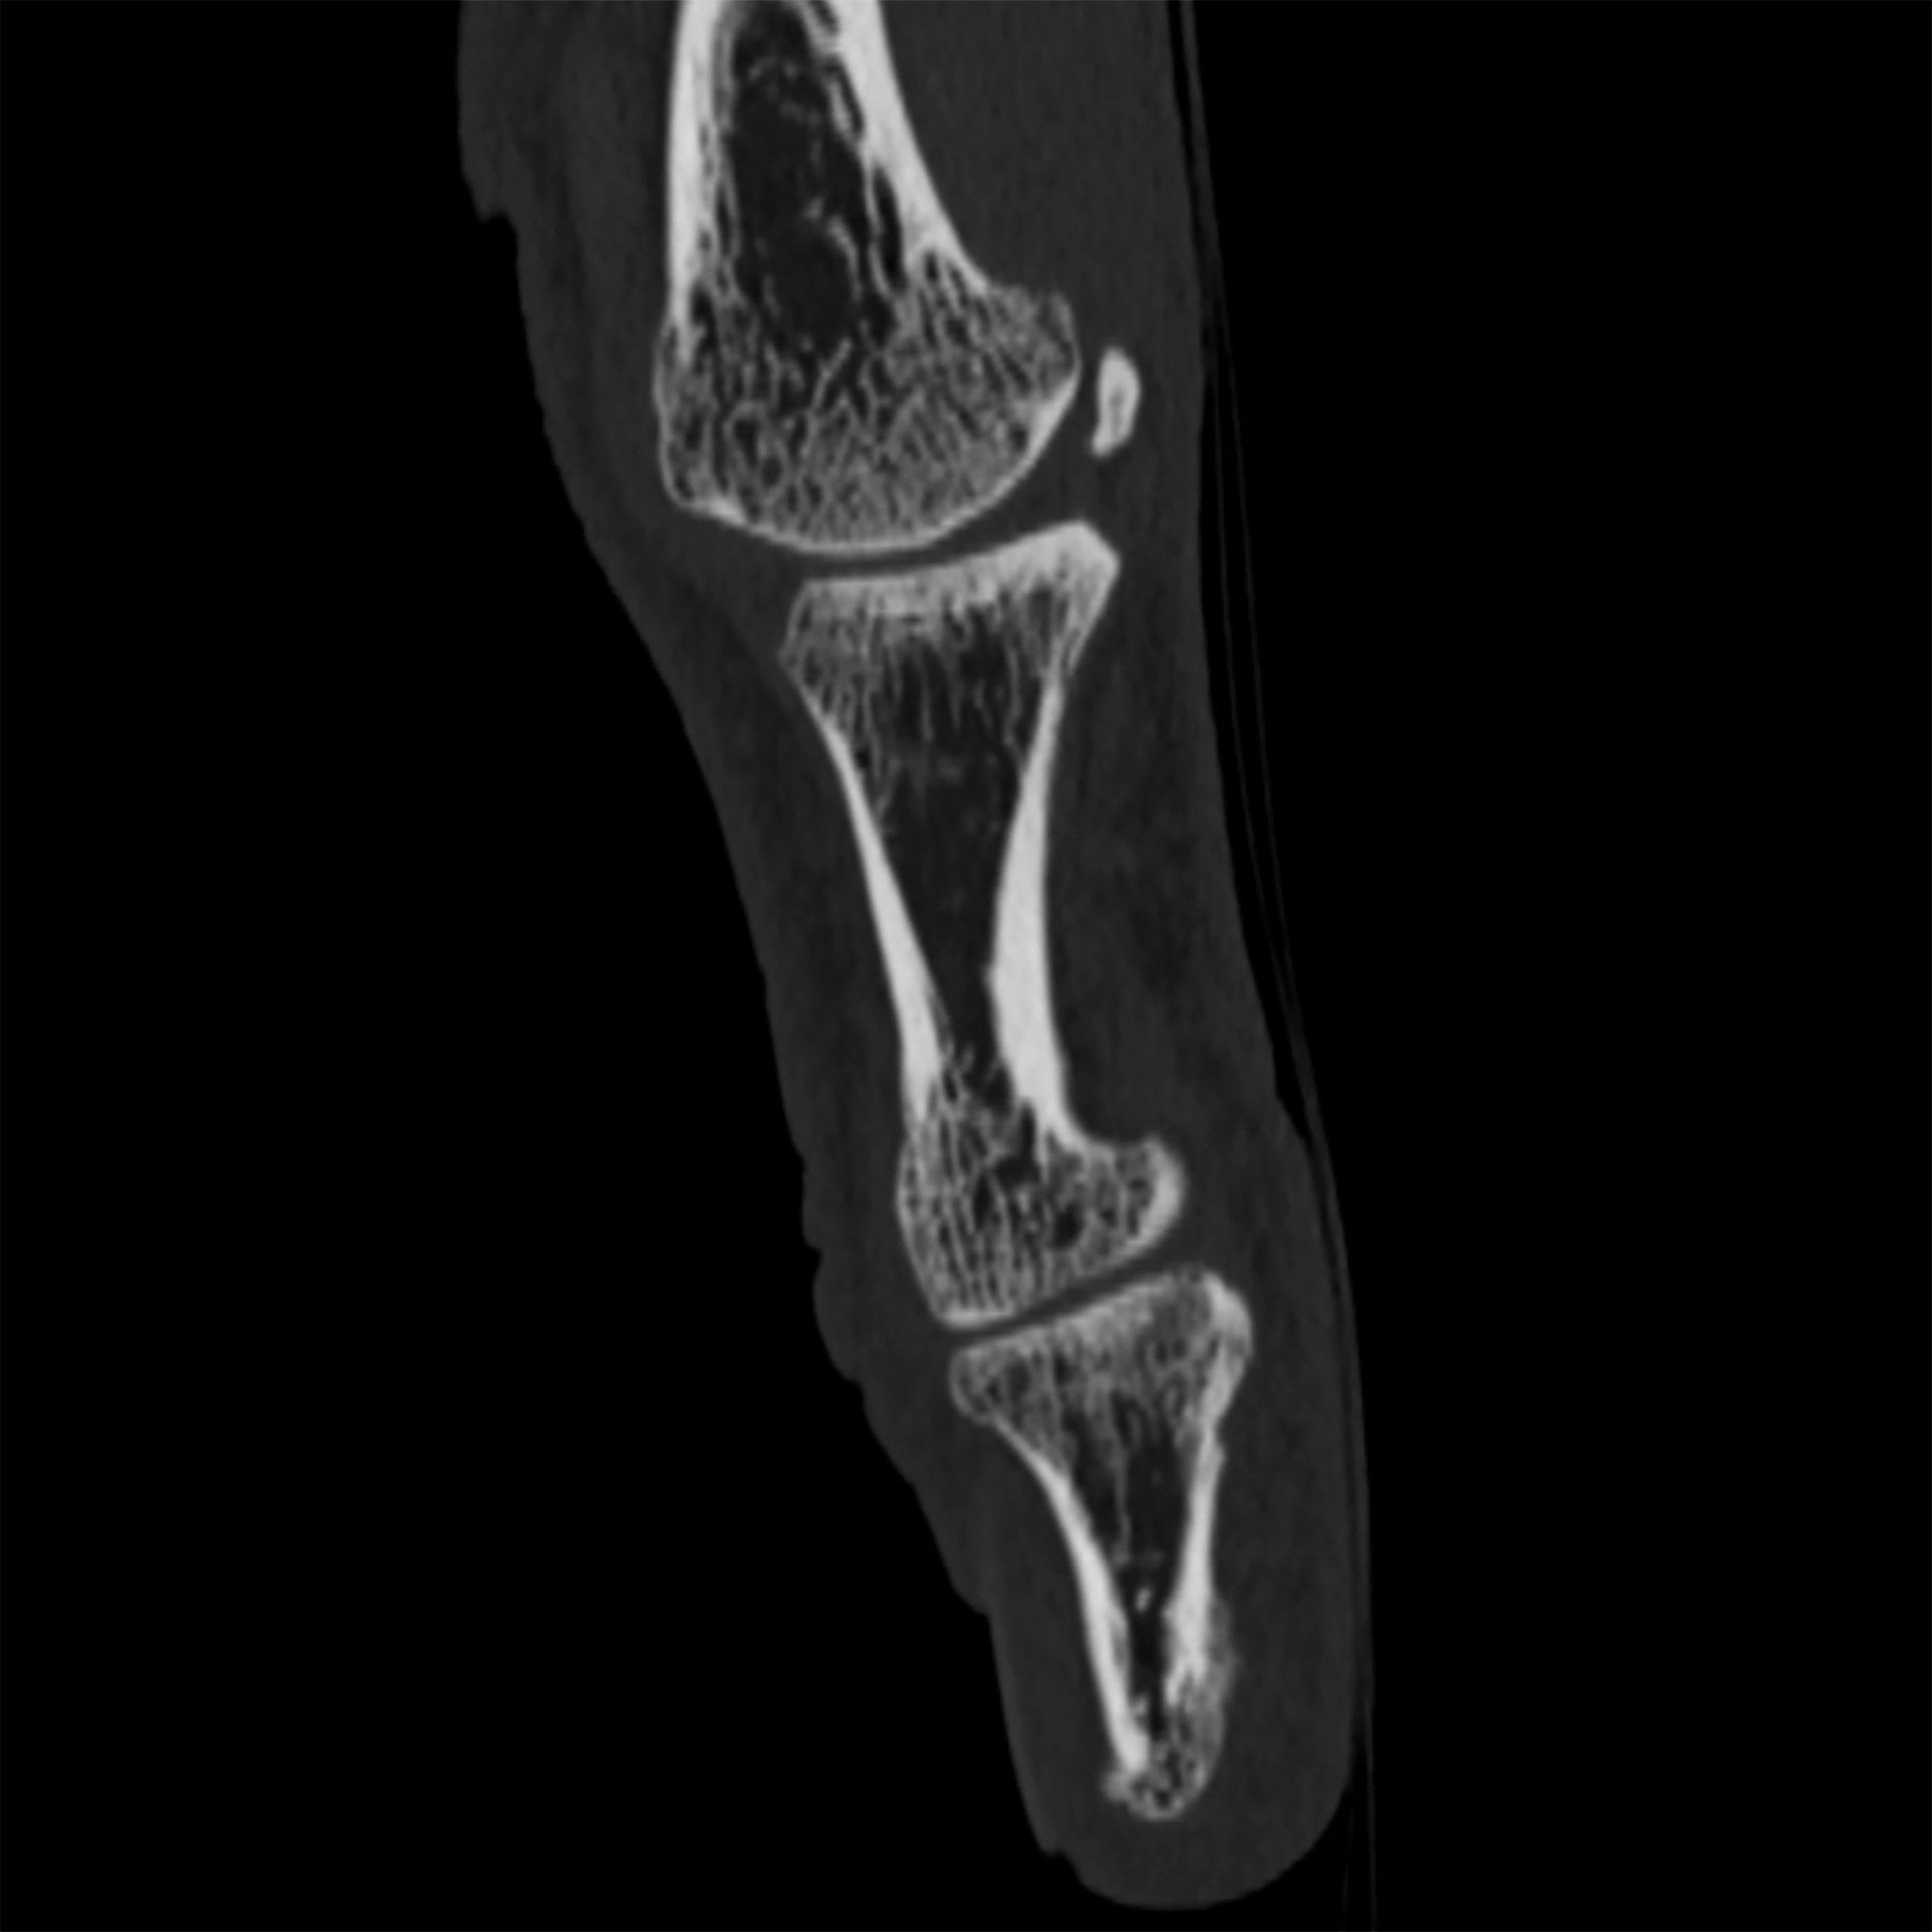

Le scanner, aussi appelé tomodensitométrie (TDM), est un examen d’imagerie médicale qui utilise les rayons X pour obtenir des images très détaillées du corps humain. Contrairement à une radiographie classique, le scanner réalise des images en coupes, comme des « tranches », permettant d'explorer avec précision une région du corps dans les trois plans de l’espace, voire en 3D.

Pendant l’examen, un tube à rayons X tourne autour de vous pendant que vous êtes allongé(e) sur une table. Des détecteurs remplacent le film radiologique et transmettent les informations à un ordinateur puissant qui reconstruit en temps réel des images très fines (moins de 1 mm).

• une visualisation précise des organes, os, vaisseaux ou poumons ;

Une fois les images réalisées, elles sont analysées par un radiologue qui interprète les résultats. Des reconstructions 3D ou volumiques peuvent être effectuées si besoin.